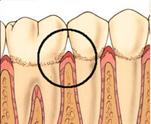

PrefGel este un gel conditionant cu pH neutru (EDTA 24% în gel de carboximetil celuloza) care îndeparteaza "smear layer"-ul restant pe suprafata radiculara dupa îndepartarea mecanica a tesutului de granulatie, placii bacteriene si a tartrului dentar, eliminarea acestui "smear layer" asigurând interactiunea si precipitarea EMD pe suprafata radiculara curata. Aceasta interactiune este vitala pentru regenerarea parodontala care include formarea de cement, ligamente parodontale cu fibre de colagen orientate functional si de os alveolar.

Utilizarea PrefGel asigura îndepartarea "smear layer"-ului si expunerea matricei colagenice a dentinei si cementului prin demineralizare selectiva si fara a afecta vitalitatea tesuturilor parodontale înconjuratoare.

Agentii demineralizanti care actioneaza la pH acid (acid citric, acid fosforic) îndeparteaza si ei "smear layer"-ul dar exista riscul ca acestia sa provoace necroza tesuturilor parodontale înconjuratoare si sa denatureze matricea colagenica.